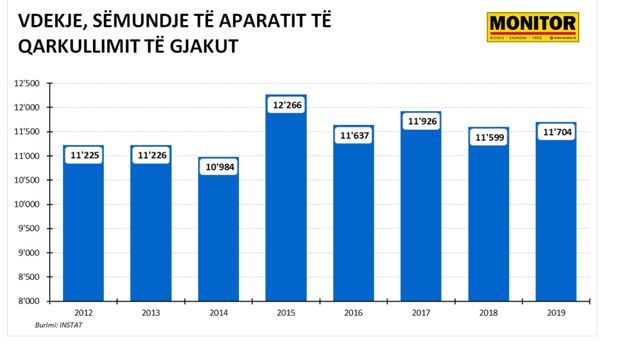

Të dhënat zyrtare të INSTAT tregojnë se më 2019-n kanë humbur jetën nga sëmundjet e aparatit të qarkullimit të gjakut 32 persona në ditë.

Në total 11,704 persona kanë humbur jetën nga zemra ose tensioni, ose 53% e totalit të vdekjeve natyrale.

Sipas INSTAT, janë rritur me 0.9% vdekjet nga sëmundje të aparatit të qarkullimit të gjakut në 2019-n, në raport me një vit më parë.